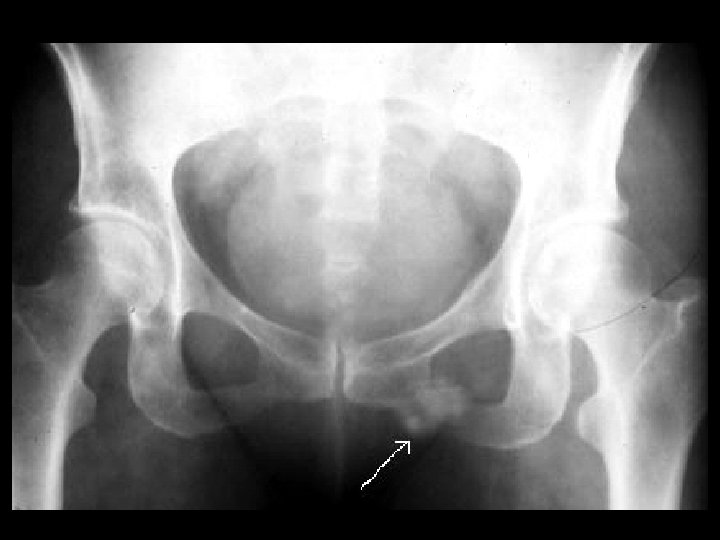

Healing stress fracture • Findings: – Fluffy density overlying the left inferior pubic ramus • ddx: – chondrosarcoma – parosteal osteosarcoma – myositis ossificans